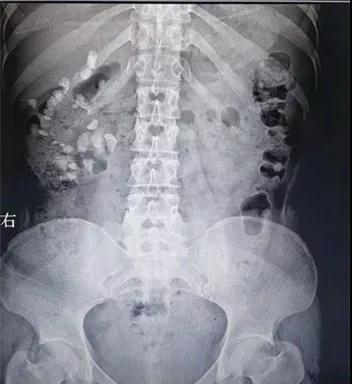

王女士今年23歲,前段時間總是腰痛難忍,一度出現(xiàn)血尿,來到徐州市礦山醫(yī)院泌尿外科就診,檢查發(fā)現(xiàn),其右腎臟上中下盞幾乎都有結(jié)石,最大的一顆直徑長2.3CM,差不多一元硬幣大小,且有腎積水。